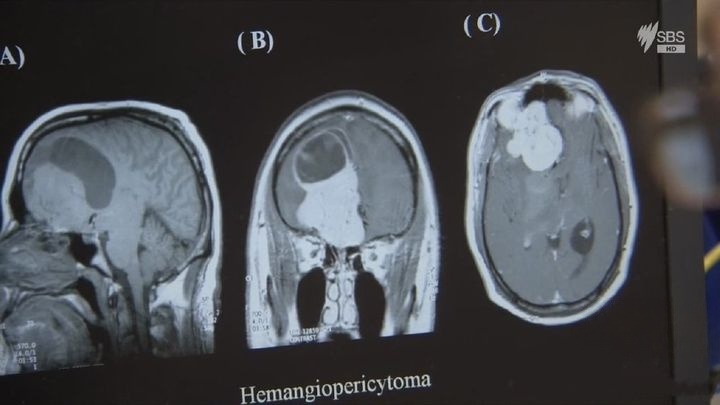

前额叶皮层的 “决策与抑制” 功能:通过功能性磁共振成像(fMRI)技术,观察行为正常者与异常者在执行 “抑制任务”(如看到特定信号时停止动作)时的大脑活动。结果显示,行为异常者的前额叶皮层(负责决策、冲动抑制的核心区域)激活程度明显低于正常人 —— 例如,在 “停止信号任务” 中,当需要抑制已开始的动作时,正常人大脑前额叶会快速活跃,而冲动控制障碍患者的前额叶活跃延迟,导致无法及时抑制不当行为;

720P 高清画质精准呈现神经研究的细节 —— 无论是 fMRI 扫描下大脑区域的激活图谱、神经元之间神经递质传递的微观画面,还是实验中被试者的行为反应,都能清晰捕捉。纪录片大量运用 “可视化技术” 简化复杂的神经科学概念:通过动画演示大脑不同区域的分工(如用不同颜色标注前额叶、边缘系统,展示它们如何协同控制行为);用 “信号传递路线图” 呈现神经递质从释放到接收的全过程;将大脑控制行为的过程类比为 “公司管理”—— 前额叶是 “管理层”,负责决策与监督,边缘系统是 “执行层”,负责落实情绪与本能反应,当 “管理层” 无力时,“执行层” 的本能行为就可能失控。这些可视化手段与通俗类比,让非专业观众也能轻松理解 “大脑如何控制行为”,避免因神经学术语产生距离感。